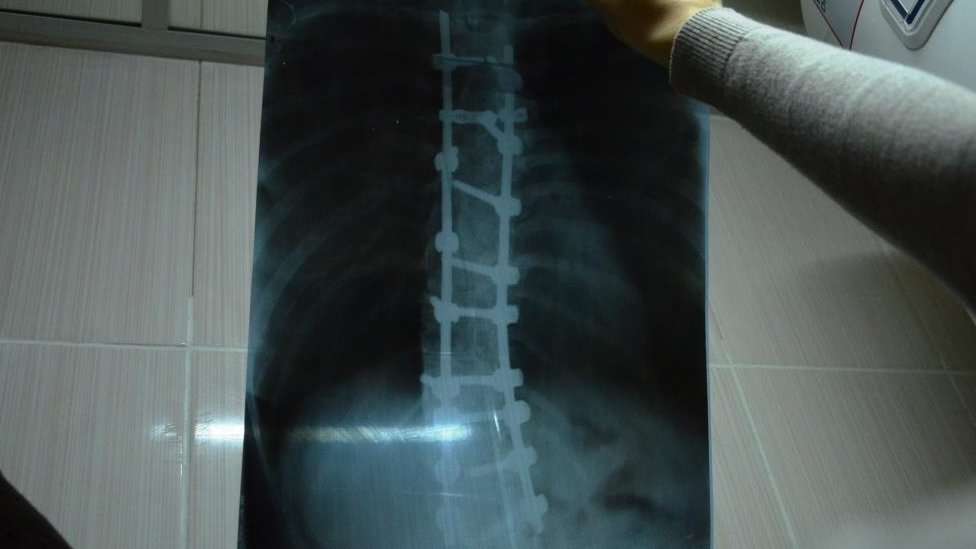

Сколіоз – захворювання опорно-рухового апарату, що характеризується викривленням хребта у трьох площинах, пов'язане з ротацією хребців навколо своєї осі.

Операція дуже складна, тому що розрізається вся спина, вставляється туди металоконструкція, закріплюються болти. Була висока імовірність, що …